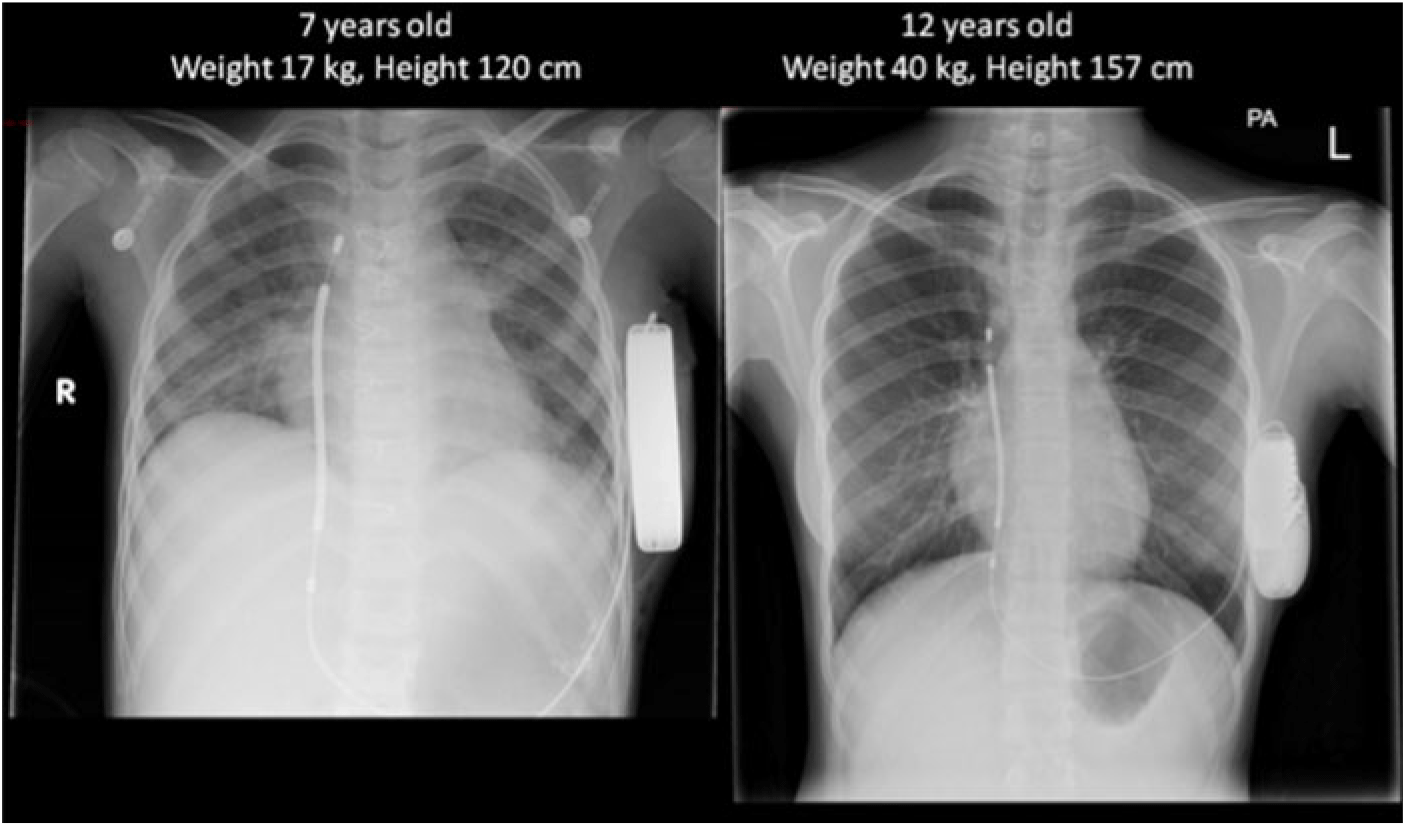

The Publisher apologises for omitting the figure below, from the publication of this paper.

Spentzou, G, McLean, A and McLeod, K. Growth and the subcutaneous implantable cardioverter defibrillator in a small child. Cardiology in the Young. Published by Cambridge University Press, 30 October 2019. doi: 10.1017/S1047951119002440.CrossRefGoogle Scholar